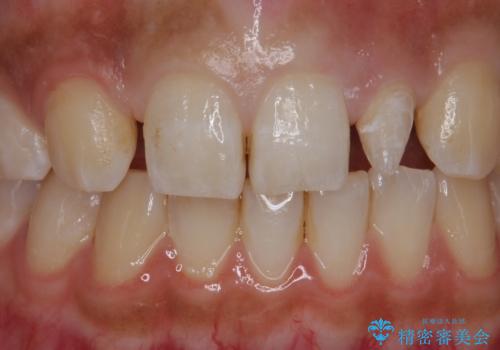

変色した前歯をキレイにしたい ジルコニアクラウンでの修復

- 左上の前歯の変色が気になるとのことで来院されました。

もともと小さい歯(矮小歯)に樹脂が盛り足されている状態でした。

今後の変色をなくすために樹脂ではなくセラミックでの治療を行います。

セラミックでの治療をすることにより今後の変色を抑えることができます。

色・形ともに改善することができ大変喜んでいただけました。